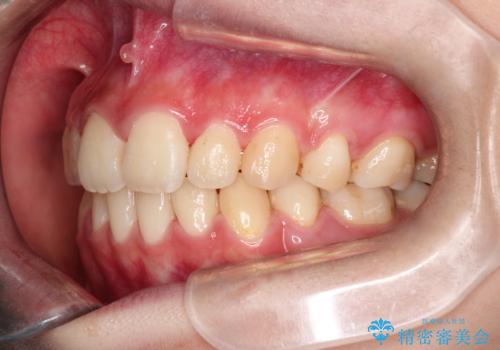

【ハーフリンガル】口元を下げたい!

- 口元が出ていることを主訴に来院されました。

歯を抜いてスペースを作ることで、前歯を下げることができました。

ハーフリンガルということで治療期間が3年近くかかりましたが、口元もしっかり下がり満足していただきました。